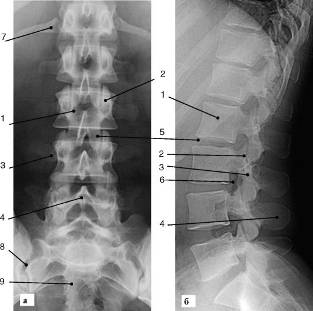

Рентгенография является одним из основных методов исследования позвоночника. Стандартные проекции при рентгенографии позвоночника - прямая и боковая. В норме позвоночник, представленный 24 позвонками, образует естественные изгибы: кпереди в шейном и поясничном отделах, кзади - в грудном и крестцовом. Эти физиологические отклонения от срединной линии видны на боковых рентгенограммах. Изучение функционального состояния позвоночника проводят путем выполнения рентгеновских снимков в боковой проекции в положении максимального сгибания, максимального разгибания и в среднем положении. Пример рентгенограмм поясничного отдела позвоночника представлен на рис. 3.

Рис. 3. Рентгенограмма поясничного отдела позвоночника в прямой (а) и боковой (б) проекциях: 1 - тело позвонка; 2 - суставной отросток; 3 - поперечный отросток; 4 - остистый отросток; 5 - пространство межпозвонкового диска; 6 - верхняя замыкательная пластинка тела позвонка; 7 - нижняя замыкательная пластинка; 8 - подвздошно-крестцовое сочленение; 9 - крестец